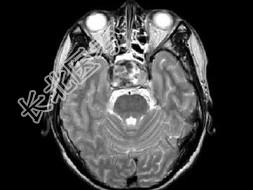

- 单项选择题男,26岁, 突发性视力障碍3天,根据所提供图像, 最可能的诊断为 ( )

D、嫌色细胞瘤(垂体瘤卒中)